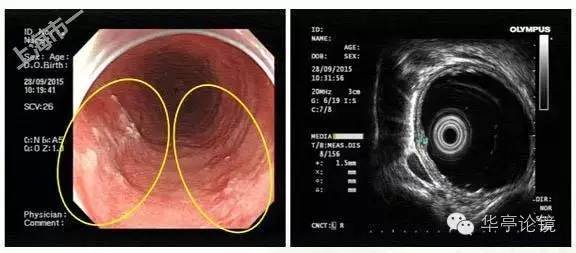

白光内镜:可见距门齿25-29cm见多片浅表糜烂,局部粘膜发白、呈粗糙不平或局部伴凹陷, 黏膜血管网紊乱或缺失。EUS提示:病变处粘膜增厚,见低回声改变,粘膜下层完整。未见周围肿大淋巴结,见下图。